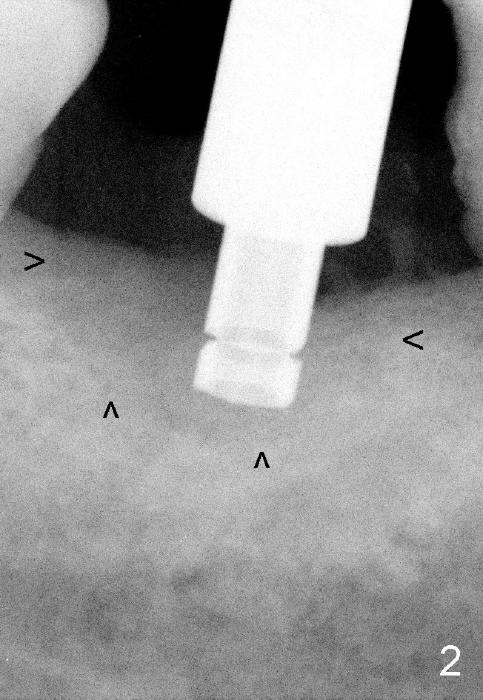

Intraop PA with a radiopaque instrument in the socket reveal the socket is large (Fig.2 arrows). The latter is filled with bone graft (Fig.3 arrows) and collagen plug (Fig.4). Fig.5 and 6 show wound healing 7 and 13 days postop. The ridge is not atrophic 4 months postop (Fig.7), ready for implant.